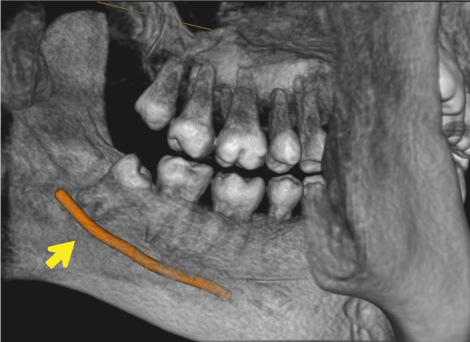

一般歯科診療では敬遠されがちな、重要神経管(下歯槽神経管:下顎の神経と動脈・静脈が入っている管)に接する親知らず

抜く方向や角度を十分にシミュレーションして安全抜歯を心がけている。